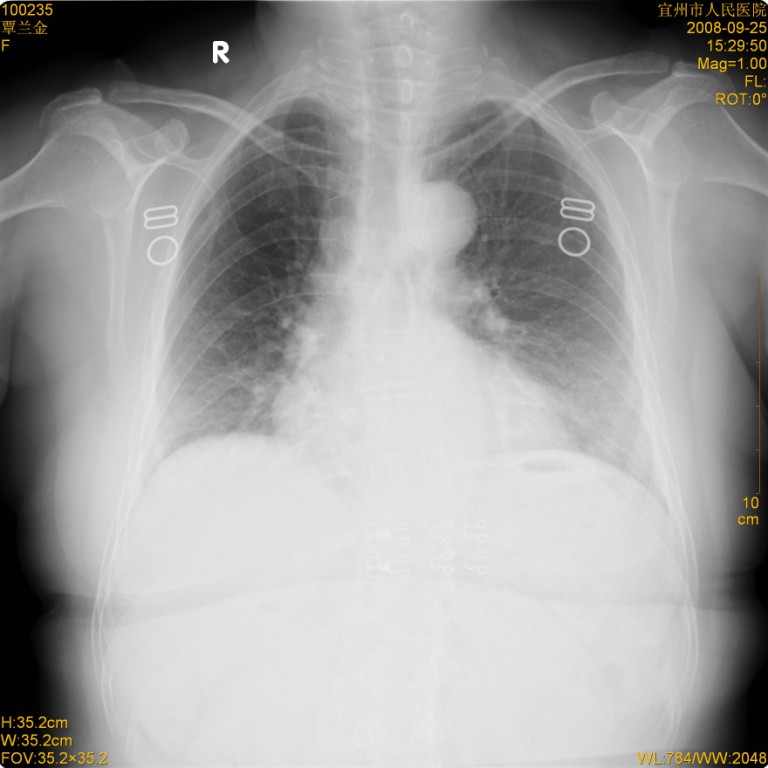

标题: CT20268:肺泡癌?间质性肺炎?

女,62岁,近二年经常咳嗽,近二个月,消瘦、乏力。

前面一张胸片是今天照的,后面一张胸片是去年9月份的。

弥漫性双肺间质纤维化。

两肺弥漫性间质性病变(间质性肺炎伴肺间质纤维化?)。